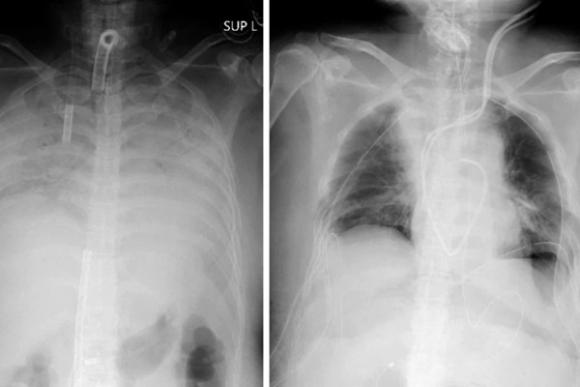

Ảnh chụp X-quang cho thấy phổi của một bệnh nhân COVID-19 trước và sau khi phẫu thuật cấy ghép. Ảnh: Bệnh viện Đại học Kyoto

Người phụ nữ nhập viện hôm 5/4 và được kết nối với một thiết bị tim phổi nhân tạo, được gọi là trao đổi oxy qua màng ngoài cơ thể (ECMO). Bà đã được ghép một phần phổi trái của chồng và một phần phổi phải của con trai hai ngày sau đó.

Toàn bộ quá trình cấy ghép phổi diễn ra khoảng 11 giờ đồng hồ tại Bệnh viện Đại học Kyoto. Các bác sĩ cho biết cả người hiến tặng và bệnh nhân đều trong tình trạng sức khỏe ổn định.